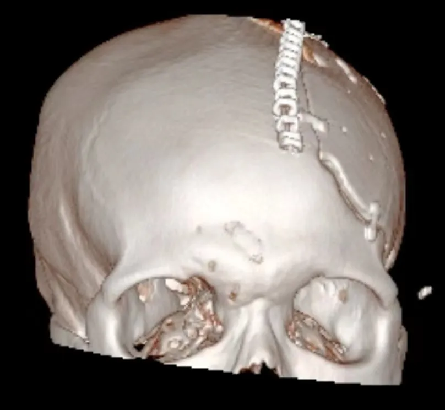

術前:

術後: